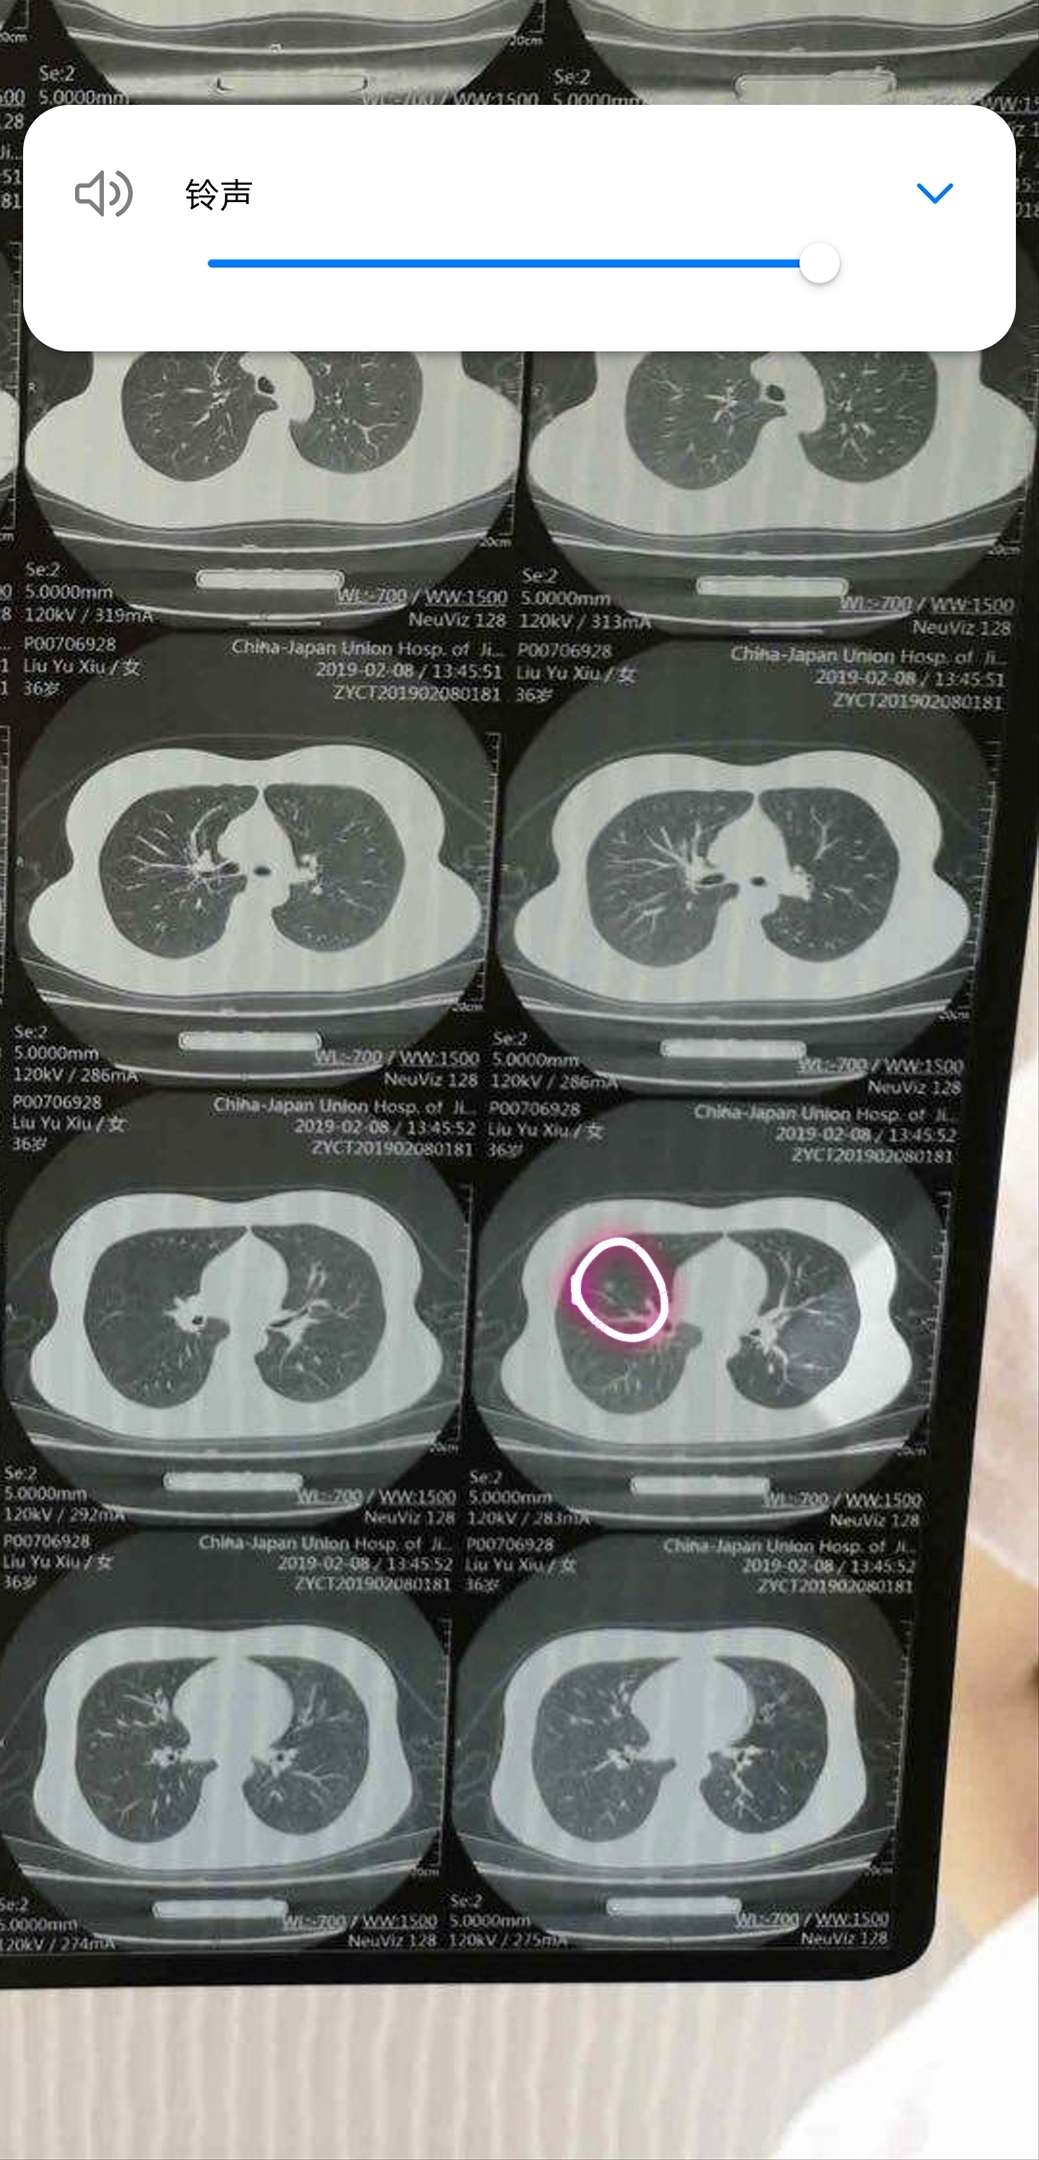

陈波医生我的意见是积极外科手术拿掉。此图像一个日冕,中间的日体和周围的光晕之间密度区分比较明显了,说明中央部分密度较高,有可能有局部浸润

有点像微乳头状磨玻璃结节